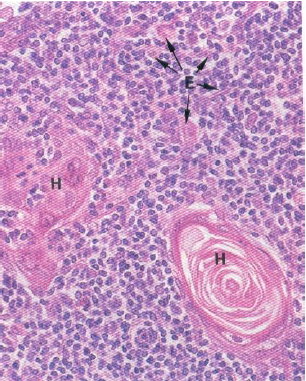

Hassall’s corpuscles

圍成同心圓的reticular cell

- fibrous capsule>trabeculae

- reticular fiber

- white pulp( Secondary lymphatic nodule)

- red pulp (other)

- central a. 被 T cell 包覆(Periarterial lymphatic sheath)

- Secondary lymphatic nodule